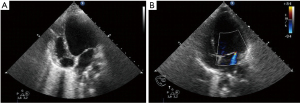

Emergency echocardiography showed massive acute left ventricular functional restriction (see Figure 1 and Table 2).

| LV-function | Massive dysfunction with: LVEDD 5.5 cm, FS 15%, EF 30%, MI III°, AoVTI 10 cm, normal wall motion |

| Ventriculography | Significant LV-dysfunction, concentric pumping without wall motion abnormalities |

On admission, the patient was hypotensive despite high doses of catecholamines. Initial ECG showed tachycardic sinus rhythm (140 bpm) with ST-depressions in II, III, augmented voltage foot (aVF) and elevations in V1–4 (see Figure 2), chest X-ray revealed pulmonary oedema (see Figure 3). Blood gases showed lactate acidosis (lactate max. 8 mmol/L, pH min. 7.22) and cardiac enzymes were highly increased (see Figure 2).

Left ventricular function and cardiac output was just sufficient to refrain from ECLS therapy. Suspecting acute viral myocarditis and to rule out coronary pathologies, cardiac catheterization including myocardial biopsies was performed. It showed severely impaired cardiac function lacking any coronary anomalies while the biopsies revealed no signs of myocarditis (see Table 2).